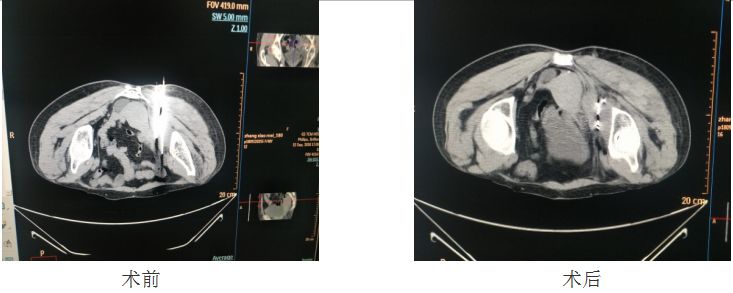

该患者2017年7月行“根治性直肠切除术+造瘘术”,术后行6周期全身静脉化疗,期间病情平稳。2018年7月患者因左下肢麻木,在某医院进行检查,考虑肿瘤转移,瘤体包绕在左侧髂内动脉,左侧梨状肌及闭孔内肌受损,并在该医院行放疗后,症状无明显缓解。为求中西医结合治疗,患者来到我院肿瘤科。入院时患者左下肢无力、麻木、疼痛、肌肉萎缩、肌力2级。肿瘤科王兰英主任、黄邦荣副主任及科室全体医师,经过反复讨论后,认为患者在其他治疗手段效果欠佳的情况下,可考虑肿瘤碘125粒子植入治疗。与患者及家属反复沟通后,9月12日,由王兰英主任主持,放射影像科王闻奇主任、唐治副主任、朱小忠老师等多位专家指导下,通过CT引导定位,黄邦荣副主任时时与专家沟通,确定穿刺无误后,首次成功为该患者实施了碘125粒子植入治疗,填补了我院实体瘤碘125粒子植入治疗的空白。术后第3天患者左下肢麻木、疼痛明显减轻、左下肢肌力4级。